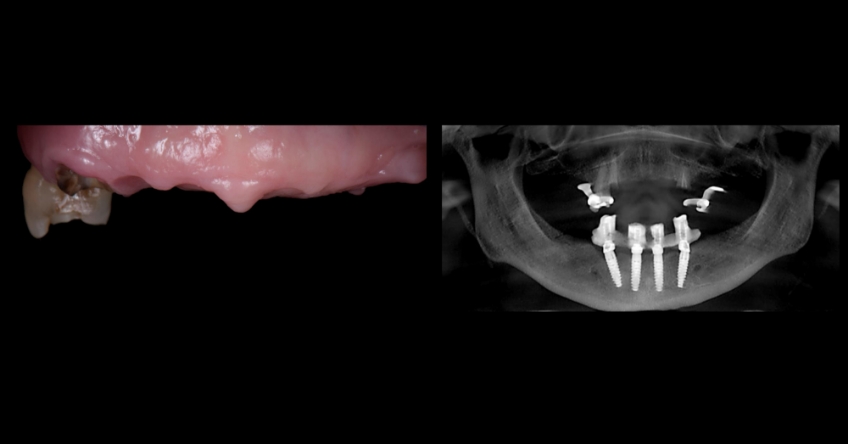

Our patient is a 66-year-old woman who presented with three remaining teeth in the maxillary arch and a fixed-hybrid temporary reconstruction in the mandible. She came looking for a second opinion regarding treating her maxillary arch.

Her previous dentist suggested a similar approach to what was done in the mandible, which entailed removing the few remaining teeth and removing bone and soft tissue to place four implants for a fixed-hybrid provisional restoration.

Even though she went through this protocol with her lower jaw, she wanted to know if there were alternatives to treat her condition in the maxilla because the bone and tissue removal aspect did not appeal to her. She was told elsewhere that this was the only predictable way of treating her condition.

Even though there were only three remaining teeth, they were so severely compromised that they were hopeless; however, their presence, as well as the support provided by the flipper type of removable provisional restoration, helped enormously in preserving a rather pleasing gingival architecture, which would be destroyed if we chose a fixed-hybrid restoration.

This makes her a lip-tooth-ridge Class I patient according to the published classification. According to Dr. Mish’s classification, she is an FPI, which means her preexisting condition is conducive for an all-white, implant-supported fixed dental prosthesis without any pink ceramics.

The challenge is that bone availability is limited to her premaxilla, so we must either graft the sinuses to incorporate distal implants or bypass the sinuses and place one ZI bilaterally. Both approaches are perfectly doable and predictable because they’re supported in the scientific peer-reviewed dental literature. They also present nuanced implications that need to be reviewed and understood by the treating team and the patient, who is the ultimate decision-maker.

Her pneumatized sinuses do not allow grafting and implant placement simultaneously. This means we would need a staged approach — perform an initial procedure limited to grafting and a subsequent procedure for implant placement.

This translates to a significant increase in treatment time and financial commitment by the patient. However, bypassing the sinuses and placing a ZI bilaterally would expedite the overall treatment time and represent a financial benefit.

Once the patient understood the nuances between graft vs. a graft-less solution, she opted for a combination of anterior and ZIs instead of grafting the sinuses.